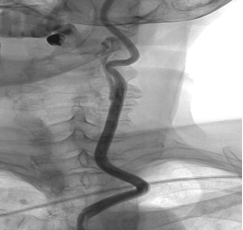

- Краткая информация о пациенте: Пациентка, 72 года. С 2016 года наблюдается по поводу аневризм левой ВСА. 15.09.2016 г. в ФГАУ «НИИ нейрохирургии им. акад. Н.Н. Бурденко» выполнена селективная церебральная ангиография. От оперативного вмешательства решено было воздержаться ввиду неблагоприятной анатомии несущего аневризму сосуда. В августе 2018 года выполнено МСКТ сосудов головного мозга, на которой выявлено увеличение размеров аневризмы кавернозного и супраклиноидного сегментов в сравнении с предыдущими данными от 30.03.2016 г. Была проконсультирована нейрохирургом клиники нейрохирургии ВМедА повторно. Было решено осуществить попытку эндоваскулярного лечения аневризм левой внутренней сонной артерии. Во время предоперационной подготовки при выполнении МСКТ-ангиографии брахиоцефальных сосудов была оценена анатомия ветвей дуги аорты и прослежен их ход в шейном отделе. Учитывая подтвержденные данные о неблагоприятной анатомии для трансфеморального доступа, было принято решение об изменении тактики хирургического лечения. Решено выполнить гибридное оперативное вмешательство: выделение левой общей сонной артерии, редрессацию патологических деформаций и эндоваскулярную имплантацию устройства, отклоняющего поток (FRED), на уровне аневризм левой внутренней сонной артерии. С учётом результатов генетического исследования на определение эффективности терапии препаратом Клопидогрел пациентке за неделю до госпитализации назначена двойная антиагрегантная терапия препаратом Плавикс 75 мг 1 раз в день и ТромбоАСС 100 мг 1 раз в день. Эффективность терапии оценена непосредственно перед началом оперативного вмешательства при помощи системы VerifyNow® — уровень подавления агрегационной функции тромбоцитов составил 36 %.

1 этап. Под общей анестезией с поворотом головы вправо выполнен линейный продольный разрез по переднему краю кивательной мышцы. Острым путем осуществлен доступ к общей сонной артерии. Общая сонная артерия взята на турникет, мобилизована дистально до уровня бифуркации.